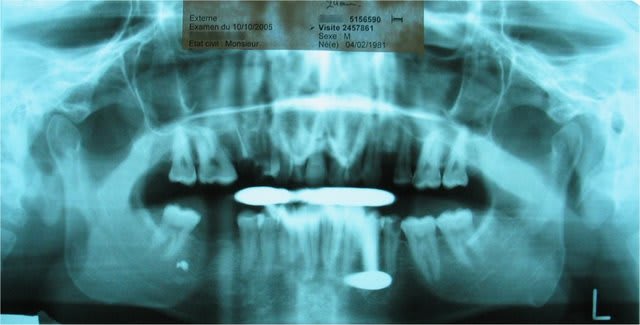

Eternelle « supraclusion », ouverture maximale de 3 mm entre incisives centrales, supérieures / inférieures, juste de quoi mettre l’embout inter dentaire pour un cliché panoramique.

Dans un premier temps, ce patient de 24 ans a été référé à un Orthodontiste ( ? ), avant d’atterrir chez un occluso.

Nombreux soins dentaires à réaliser, mais le relâchement musculaire doit précéder la dentisterie opératoire.

Donc, depuis Lundi 10 octobre 2005 (msg écrit le lendemain 11/10/05 de la consultation), un patient crève de mal au GONIAQUE (et non sur la « dent 35 ») à cause d’un « trismus gauche », ou « contracture douloureuse et momentanément irréversible du muscle masséter gauche » : O.B. inter-incisives = 3 mm maximum, juste de quoi faire la pano. Celle-ci est indispensable pour vérifier (diagnostic différentiel) que le patient n’a pas une pochette surprise systémique avec, par exemple, des métas au niveau du corps / branche de la mandibule.